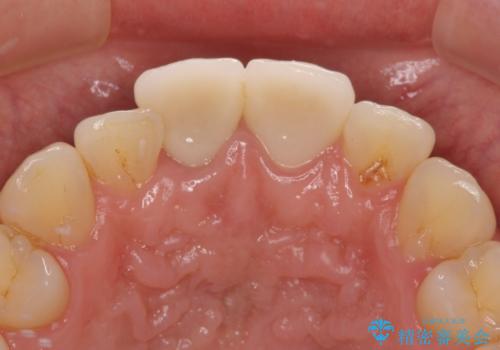

転んで欠けてしまった前歯 抜歯を回避してオールセラミッククラウンで審美回復

歯をぶつけてから1年後のレントゲン写真を取りましたが、どちらの歯も大きな異常は認められませんでした。

今後も定期的にレントゲン写真による経過観察が必要となります。